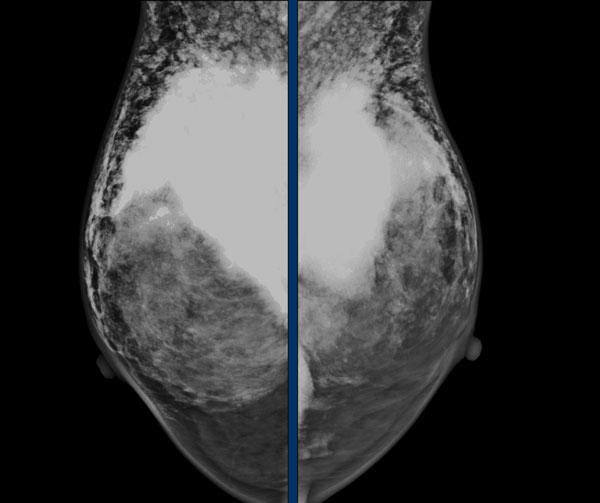

Cùng một bệnh nhân trước và sau khi đặt túi ngực trước cơ ngực (prepectoral).

Đặc biệt, túi ngực đặt trước cơ ngực có thể làm giảm khả năng đánh giá trên nhũ ảnh.

Tuy nhiên, chụp nhũ ảnh thông thường và chụp cắt lớp tổng hợp 3D (3D tomosynthesis) vẫn có thể thực hiện tốt và thực tế có giá trị tiên đoán dương tính (PPV) cao nhất trong việc phát hiện silicon ngoài bao xơ.